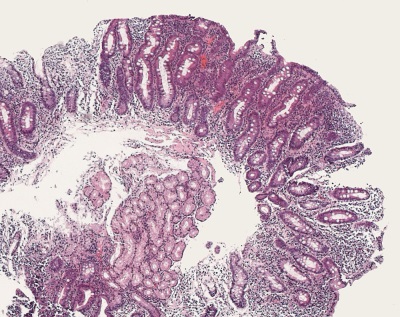

Duodenal biopsy from a patient with coeliac disease. Complete atrophy of the villi with flat mucosa and marked crypt hyperplasia. Intraepithelial lymphocytosis. Dense mixed inflammatory infiltrate in the lamina propria.

Duodenal biopsy from a patient with coeliac disease. Flat mucosa with hyperplastic crypts and dense cellular infiltrate in the lamina propria. Increased number of intraepithelial lymphocytes and vacuolated superficial epithelial cell vacuolated superficial epithelial cells. Higher magnification image on the right.